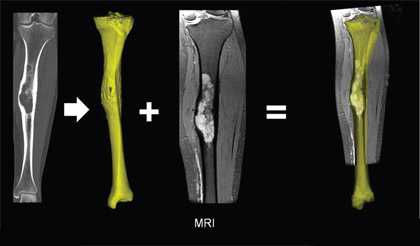

При помощи спиральной компьютерной томографии (СКТ): диагностирует в большинстве случаев. На срезах хорошо видна опухоль, ее «сетчатая» структура, хорошо различаются утолщенные костные балки, уплотнение кости по контуру гемангиомы.

При помощи магнитно-резонансной томографии (МРТ): в наиболее часто встречаемых случаях. На МРТ-сканах гемангиома, как и многие другие сосудистые структуры, дает отличный от костного МР-сигнал. Интенсивность сигнала зависит от скорости кровотока в самой гемангиоме.

Морфология, локализация и биологическое поведение

Морфологически различают первичную внутрикостную гемангиому и гемангиомы мягких тканей, вторично поражающих кости черепа (гемангиоматоз). Первичные внутрикостные гемангиомы растут медленно, как правило, расположены в губчатой кости. В большинстве они доброкачественные, но редко могут быть локально агрессивными. На КТ определяется рассасывание губчатого вещества с наличием радиальных костных балок. Гемангиома медленно растет (5-6лет), иногда самопроизвольно прекращает рост, сопровождаясь жировой инволюцией.

Гемангиома в плоских костях черепа - не частое образование, которое располагается преимущественно в диплоическом слое. Имеется разряженное строение губчатого вещества и толстые костные трабекулы, радиально расходящиеся в стороны. Очаг разряжения губчатого вещества в толще диплоического слоя определяется как зона↓плотности на КТ (стрелка на рис.1221) и↑МР-сигнала на Т2 и Flair (головки стрелок на рис.1219-1221).

Гемангиомы позвонков представляют собой очаговые образования, без масс-эффекта, вызывающие рассасывание большинства вертикальных балок позвонка, однако сохраняющиеся балки склерозируются и утолщаются. В целом вертикальная резистентность позвонка снижается, что может осложняться патологическими переломами. Считается, что гемангиома, содержащая большое количество жира, с меньшей вероятностью, будет расти или станет клинически значимой [87].

Гипертрофированные вертикальные балки губчатого вещества превосходно видны на КТ (рис.1227 и головки стрелок на рис.1225,1226).